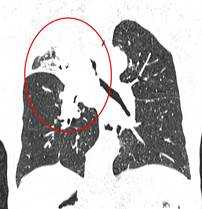

Метастазы в легких — фото рентгенограммы. Округлые тени — метастазы рака пищевода. Хорошо виден большой узел округлой формы вблизи переднего отрезка 2-го ребра. На снимке справа - циркулярное сужение пищевода за счет опухолевого утолщения его слизистой оболочки.

Как выглядят метастазы в легких на рентгене? Слева — узловые образования у пациента с раком яичка. Справа - метастазы рака яичников гематогенного характера с выраженным опухолевым лимфангиитом (обратите внимание на деформированный сетчатый, линейный характер легочного рисунка).